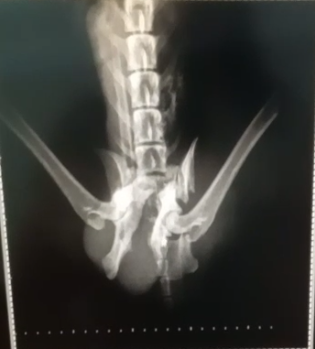

No dia 03/09/2025, o Raposinha foi atropelado. Nos exames preliminares, foram constatadas várias fraturas na região lombar, que atingiram ambas as patas traseiras e causaram compressão do canal retal. O estado de saúde dele é considerado grave, mas, enquanto for feita a cirurgia o quanto antes, há boas chances de recuperação. Caso o procedimento seja adiado, corre-se o risco de necrose dos tecidos internos e até a perda da vida.

Segue em anexo o orçamento detalhado e o laudo clínico: